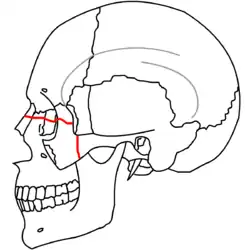

A principios del siglo XX, René Le Fort trazó ubicaciones típicas para las fracturas faciales, éstas ahora son conocidas como I, II y III fracturas de Le Fort (derecha).[5][2][6]

La Fractura de Le Fort#Lefort III, también llamada disyunción craneofacial y fractura facial transversal,[7][11] cruza la parte delantera del maxilar superior e implica al hueso lacrimal, a la lámina papirácea, y a la cavidad orbitaria, y a menudo implica al hueso etmoides,[9] es la más grave.[12] Las fracturas de Le Fort, que representan del 10% al 20% de las fracturas faciales, a menudo son asociadas con otras lesiones graves.[9]

Le Fort hizo sus clasificaciones basadas en el trabajo con cráneos de cadáveres, y el sistema de clasificación ha sido criticado por impreciso y simplista ya que la mayoría de las fracturas del tercio medio facial implican una combinación de las fracturas Le Fort.[9] A pesar de que la mayor parte de las fracturas faciales no siguen los patrones descritos por Le Fort de forma precisa, el sistema todavía se utiliza en la clínica para clasificar las lesiones.[13]